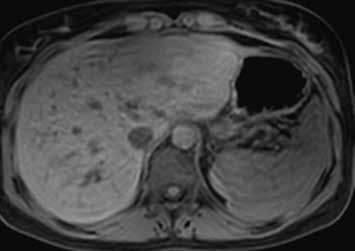

Nativně je v játrech ložisko, které je na CT hypodenzní (4), na MR izointenzní (5).

Na CEUS je v arteriální fázi patrný v levé polovině obrázku typický centrifugální charakter sycení ložiska, které je vidět v pravé polovině obrázku v B -módu (jako hypoechogenní) (6–8). Na CT (9) i MR (10) se ložisko (z obr. 4, 5) sytí homogenně, vyjma centrální vazivové jizvy, která zůstává hypodenzní.

V portovenózní fázi je ložisko izodenzní na CT (11), respektive izointenzní na MR (12).

V pozdní fázi je charakter ložiska stejný a nedochází k jeho vymývání ani na CT (13), ani na MR (14).

V centrální části ložiska je patrná vazivová jizva, která zůstává v arteriální fázi hypodenzní (9) a sytí se v pozdní fázi, kde je oproti zbytku ložiska hyperdenzní (13). Na MR je v T1-váženém obraze vazivová jizva hypointenzní (15), v T2-váženém obraze hyperintenzní (16).